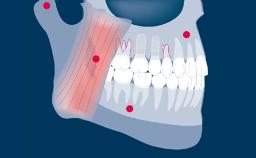

O projeto de todas as próteses sobre implante deve ser baseado em um plano protético e deve abordar todos os fatores de planejamento específicos identificados como relevantes. Há vários aspectos que são comuns ao planejamento da maioria das próteses fixas sobre implante (ou PFs), e é útil organizar esses pontos em uma sequência lógica de planejamento. O primeiro ponto é a seleção do tipo e configuração da PF. O próximo ponto é a seleção do método de retenção, seguido da consideração dos aspectos externos e da estrutura interna necessária para abordar fatores como estética, função e força. Este módulo examinará cada um desses pontos de planejamento, por sua vez. Os Módulos de Aprendizado da Academia, mais detalhados e separados, baseiam-se no presente Módulo e abordam a seleção de materiais restauradores para a PF, a seleção de pilares e a configuração dos implantes.

- estrutura interna